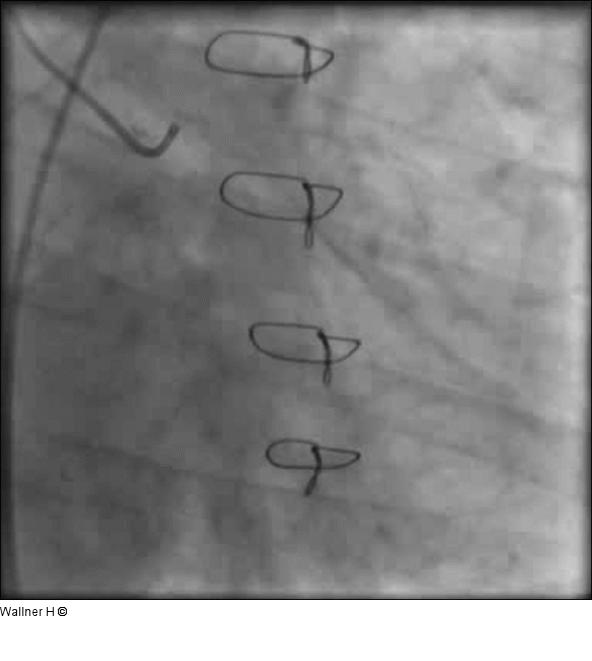

Abbildung 1: Linkes Kranzgefäß (LAO 30°/20°) Signifikante Hauptstammstenose, proximaler Verschluß der Arteria circumflexa, Konkurrenzflußphänomen bei inserierendem LIMA-Bypass. |

Signifikante Hauptstammstenose, proximaler Verschluß der Arteria circumflexa, Konkurrenzflußphänomen bei inserierendem LIMA-Bypass. |